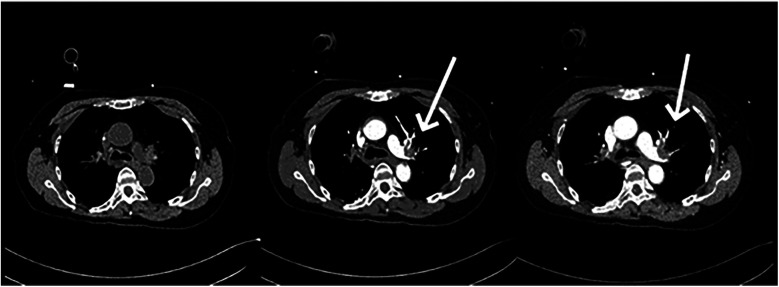

Postoperative pulmonary embolism (PE) poses a serious threat to a patient's life. However, cases involving concurrent liver rupture are exceedingly rare. This report describes a case of a patient who experienced cardiac arrest due to PE following lower extremity varicose vein surgery, followed by liver rupture during cardiopulmonary resuscitation (CPR). Under the timely intervention of a multidisciplinary team (MDT), the patient underwent extracorporeal membrane oxygenation (ECMO)-assisted resuscitation and hepatic repair surgery. Through a staged anticoagulation strategy, a balance was achieved between bleeding control and thrombosis prevention. Ultimately, after 23 days of treatment, the patient regained consciousness and was transferred to rehabilitation.